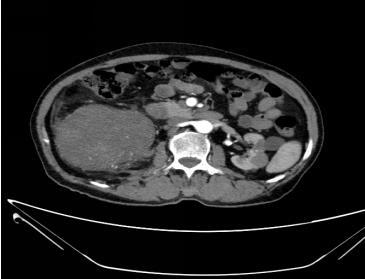

患者黃某, 71歲, “反復(fù)頭暈1年余”到我院內(nèi)科治療。入院常規(guī)腹部彩超發(fā)現(xiàn):雙腎囊腫,雙腎結(jié)石。增強(qiáng)CT診斷提示右腎下后方多發(fā)實(shí)質(zhì)性占位病變,考慮為腹膜后惡性腫瘤(肉瘤可能大)。經(jīng)外二科會(huì)診后,轉(zhuǎn)入外二科治療。

腫瘤CT表現(xiàn)